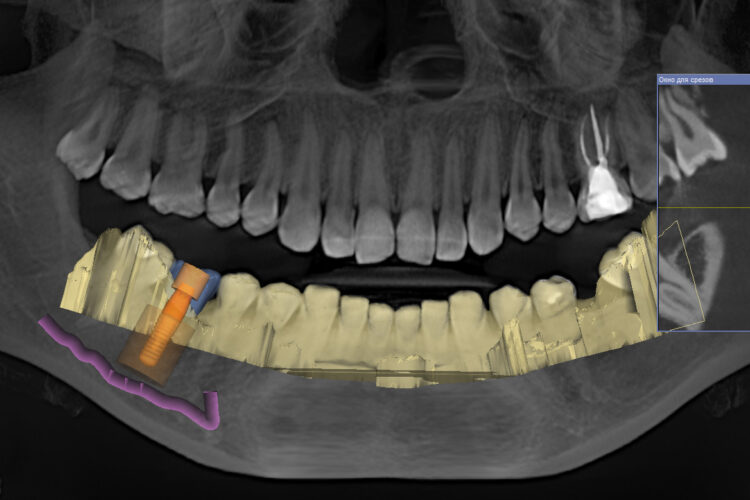

Осложнения после или во время имплантации могут быть из-за того, что хирург затрагивает анатомические образования, которые расположены на верхней и нижней челюсти. Например, устанавливая имплантат на верхней челюсти можно «промахнуться» и установить имплант прямо в гайморову пазуху. Конечно, можно выйти из этой ситуации: извлечь этот имплантат и установить большего размера, но при этом, более короткий имплант.

Еще осложнения могут быть, например, когда при установке импланта на нижней челюсти затрагивается (или сжимается) нижнечелюстной нерв. В такой ситуации у пациента появляются сильные болевые синдромы. Здесь, опять же, необходимо извлечь имплант. Но, самое страшное, что установка импланта с повреждением нерва влечет за собой онемение подбородка и щеки, которое может длиться долгое время, иногда годами.

Кроме нижнечелюстного нерва, при установке имплантата на нижней челюсти есть риск повредить артерию в подъязычной области. Кровотечение после повреждения артерии очень интенсивное, его сложно остановить, но самое страшное, что эту артерию сложно поймать. Потому что, когда артерия разрывается, она сокращается и буквально улетает в подъязычное пространство.

Все эти случаи могут возникнуть в результате неправильной диагностики и планирования имплантации, когда врач не уделил должного внимания изучению КТ пациента и планированию.

- Рентгенодиагностика. Ранее она включала в себя прицельный рентгеновский снимок или ортопантомограмму. Минус этих снимков заключается в том, что у них есть погрешность до 8 мм, то есть на панорамном снимке, если мы берем анатомические образования (нижнечелюстной нерв, гайморову пазуху) мы не сможем правильно подобрать имплантат и соответственно правильно спланировать такую операцию. При появлении компьютерной томографии у нас погрешность (в зависимости от томографа) в среднем 1 мм. И этот один миллиметр позволяет нам спланировать качественную имплантацию. В современных компьютерных томографах мы можем подобрать по специальной базе имплантатов имплантат любой длинны и диаметра, любого производителя.

При помощи диагностического аппарата (компьютерный томограф) мы изучаем толщину кости, плотность кости и определяем, будем ли использовать костную пластику.